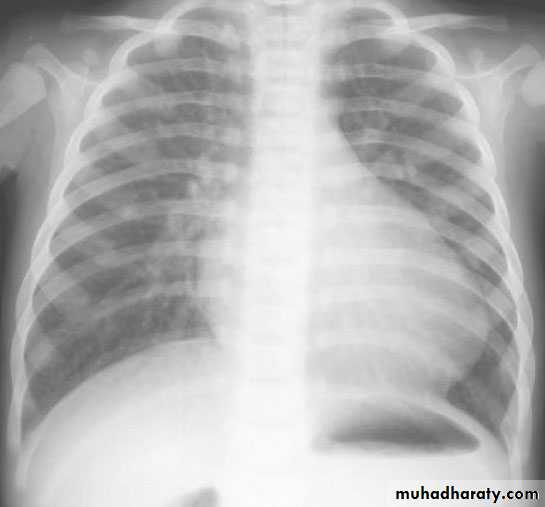

Imaging studies

ECG : RAD &RVH

CXR : Boot-shaped heartComplications: